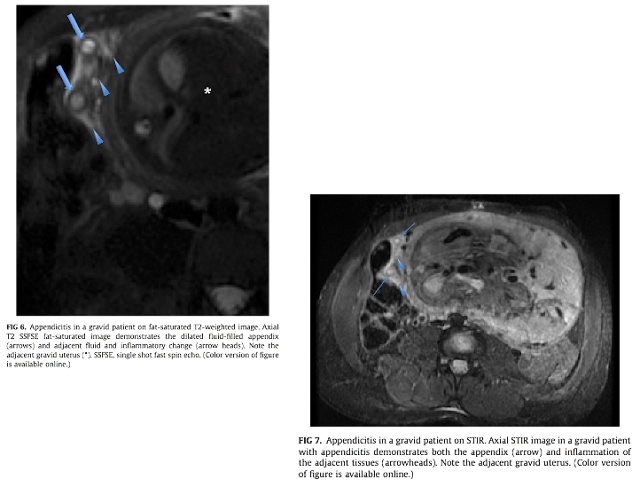

エコーで診断がつかない場合はMRIを考慮する

・特に妊娠初期におけるMRIは虫垂の描出能は良好(USでも初期ほど虫垂は描出しやすい)

・USで診断がつかない場合のMRI検査は, 感度 80%[44-98], 特異度 99%[94-100]で虫垂炎を評価可能